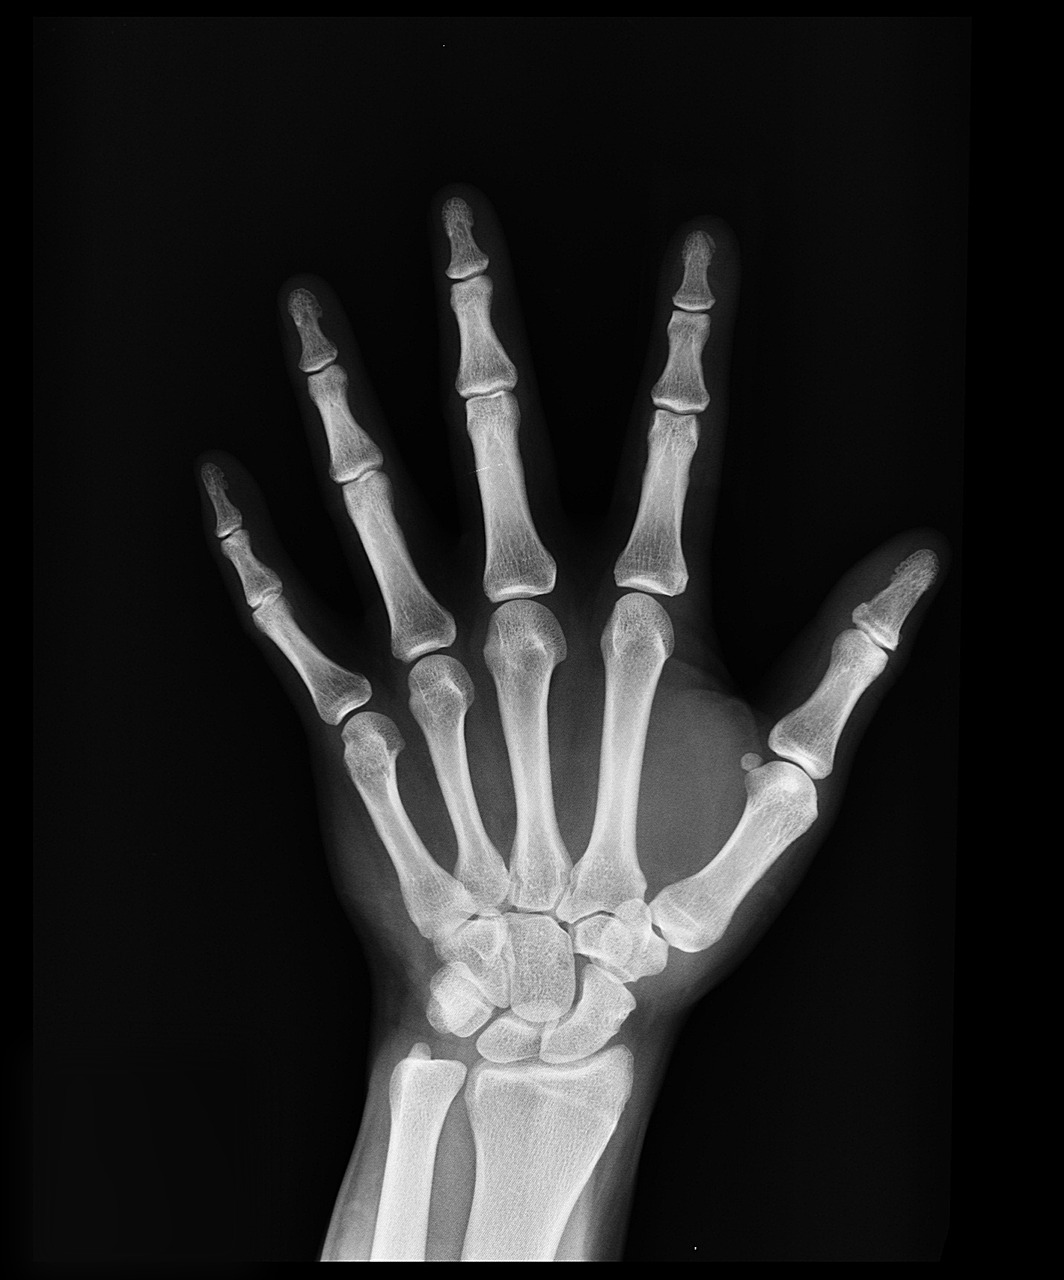

Osteoporose ist eine Erkrankung, bei der die Knochen porös werden und leicht brechen. Ganzheitliche Osteoporose Behandlung und alternative Knochenschwund Verfahren im Dürener-Kreis zwischen Köln und Aachen.

Osteoporose wird auch Knochenentkalkung oder Knochenschwund genannt und ist eine der häufigsten Knochenerkrankungen bei älteren Patienten.

In Deutschland leiden Millionen Menschen daran, besonders ältere Frauen. Bei den Betroffenen baut sich die Knochensubstanz verstärkt abgebaut. Dadurch werden die Knochen immer instabiler und brüchiger.

Die Knochendichtemessung in Düren ist eine Niedrigdosis-Röntgenuntersuchung, bei der die „Dichte“ des Knochens, d.h. sein Mineralgehalt, gemessen wird. Die ermittelten Werte werden mit Standardwerten einer 30-jährigen gesunden Frau verglichen. Die Angabe erfolgt mit dem T-Score.